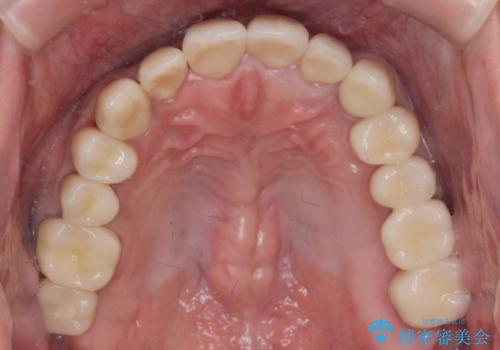

[メタルフリー] 虫歯・銀歯だらけの口腔内を全顎治療

![[メタルフリー] 虫歯・銀歯だらけの口腔内を全顎治療の症例 治療後](https://seimitsushinbi.jp/wp/wp-content/uploads/2025/03/530cf6cca6451bc106a9fb69dd58908a-500x350.jpg?v=1741918343)